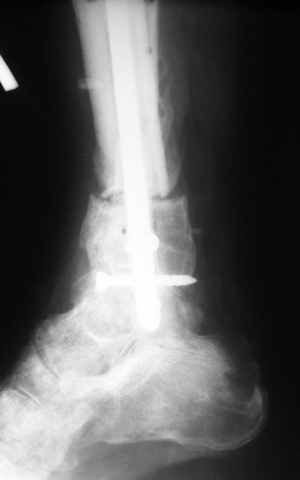

В случае гладкого заживления раны, при условии положительного решения вопроса с металлом, планируем перемонтаж аппарата Илизарова, дополнительную резекцию дистального отломка, выведение полокости голеностопного сустава в правильное положение (см. боковую Р-грамму), одномоментно остеотомия большеберцовой кости. После восстановления длинны голени, по всей видимости, артродез голеностопного сустава.

Рентгенограммы прилагаются. Фото местного статуса выложу в ближайшее время.

Ерсин, мы тоже имеем опыт такой фиксации. Подобную операцию за последние 3 года мы сделали трем пациентам. Снимки одного из них я прилагаю.

К сожалению, ни в одном из этих 3-х случаев мы не получили удовлетворяющего нас результата. Очень трудно провести штифт, введенный антеградно ровно по центру таранной кости. Отсутствие подвижности между диафизом и дистальным отломком большеберцовой кости (после фиксации в аппарате в течение 1-2 мес) очень усложняет проведение штифта в центр блока таранной кости. Поэтому мы от этого пока отказались, и проводим штифт через пятку. При данном варианте фиксации подобных проблем не возникало ни разу.